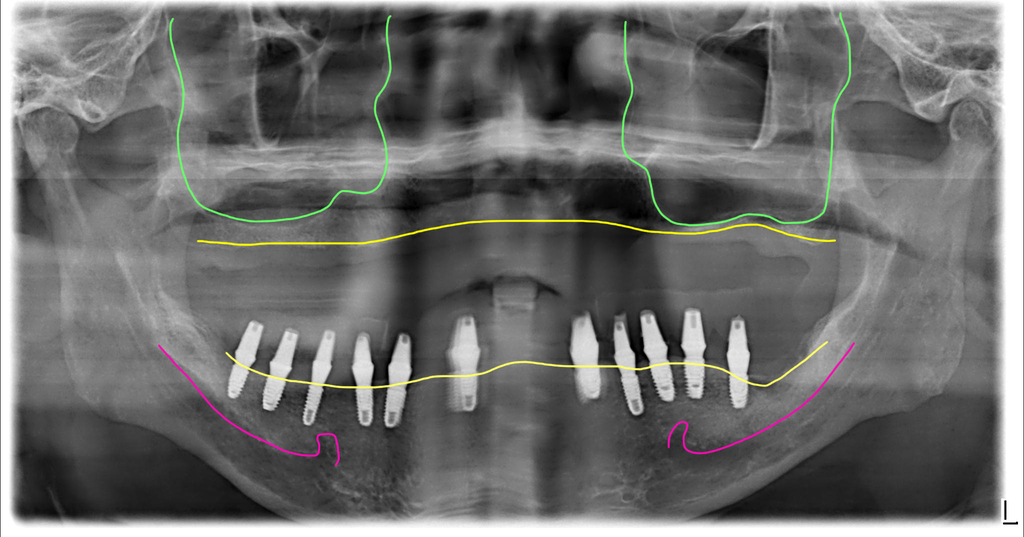

아 그리고, 이 분은 하악골의 뼈가 너무 좁아서 네비게이션 수술이 꼭 필요했던 분이었어요. 보통 하악골은 이렇게까지 얇은 분은 드물지만 이렇게 좁고 딱딱한 뼈에는 더 많은 주의를 기울여서 수술을 해야 합니다.

치료전후 CT 비교사진입니다. 겨우 뼈 속에 임플란트를 위치시켜서 완성한 모습이에요. 네비게이션이 도움이 된 수술입니다.